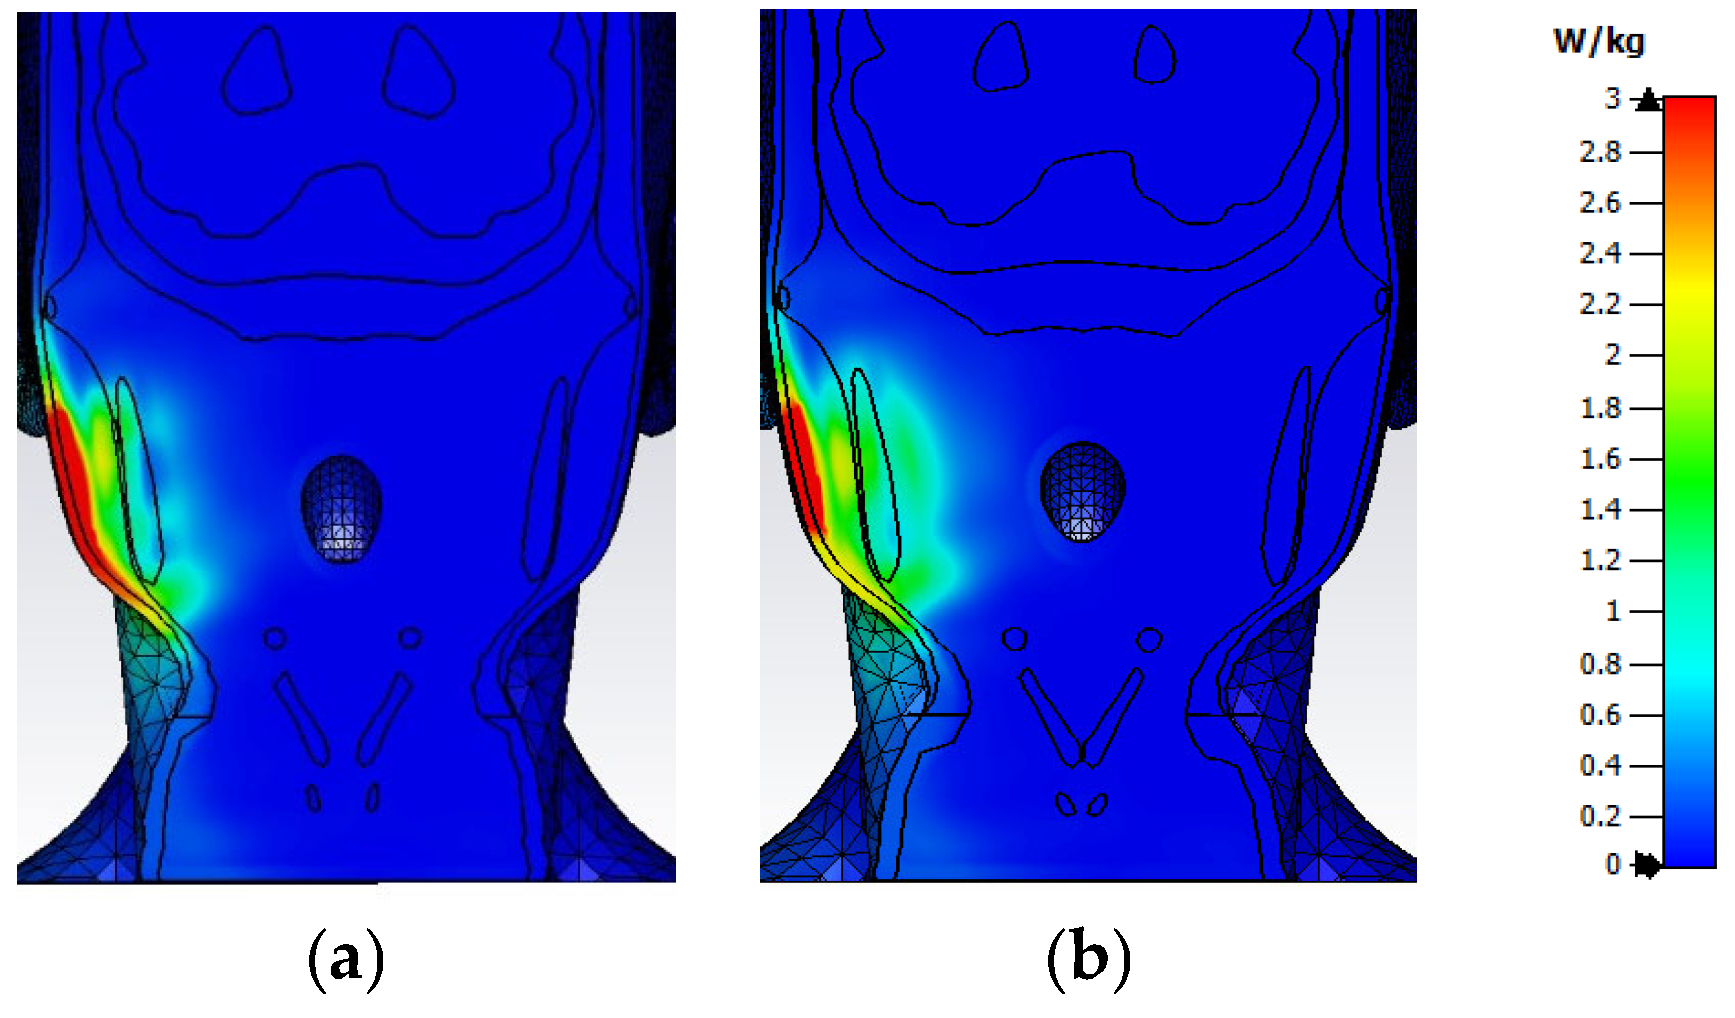

3.2. Distribution of SAR Values Within the Model of the Head of a User

3.3. Impact of the Face-to-Phone Distances on the Electric Field and SAR Distribution in the Implant Vicinity